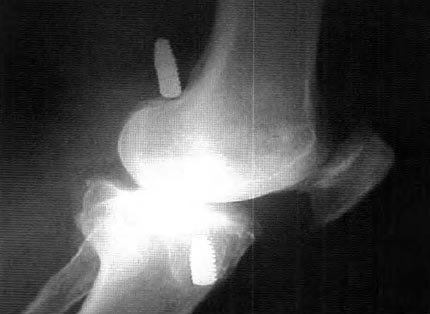

En cuanto a las causas técnicas, lamás frecuente que ocurrió en 20 de los 24 pacientes (83 %), se relacionó con la posición anterior del hoyo femoral, lo cual pudimos ver y suponer radiográficamente y certificar durante la cirugía de revisión, al observar el remanente de una pared posterior de entre 5 a 6 mm, cuando lo que consideramos normal es de 1 a 2 mm. (Fig. 2), mientras que en 2 de los pacientes, la falla tecnica se debió a la posición demasiado posterior del hoyo femoral, con la consecuente ruptura de la pared posterior, hecho que pasó inadvertido durante la cirugía y que posteriormente fue constatado mediante el control radiográfico, visualizándose el tornillo por fuera del cóndilo femoral. (Fig.3)

Figura 3: Ruptura de la pared posterior